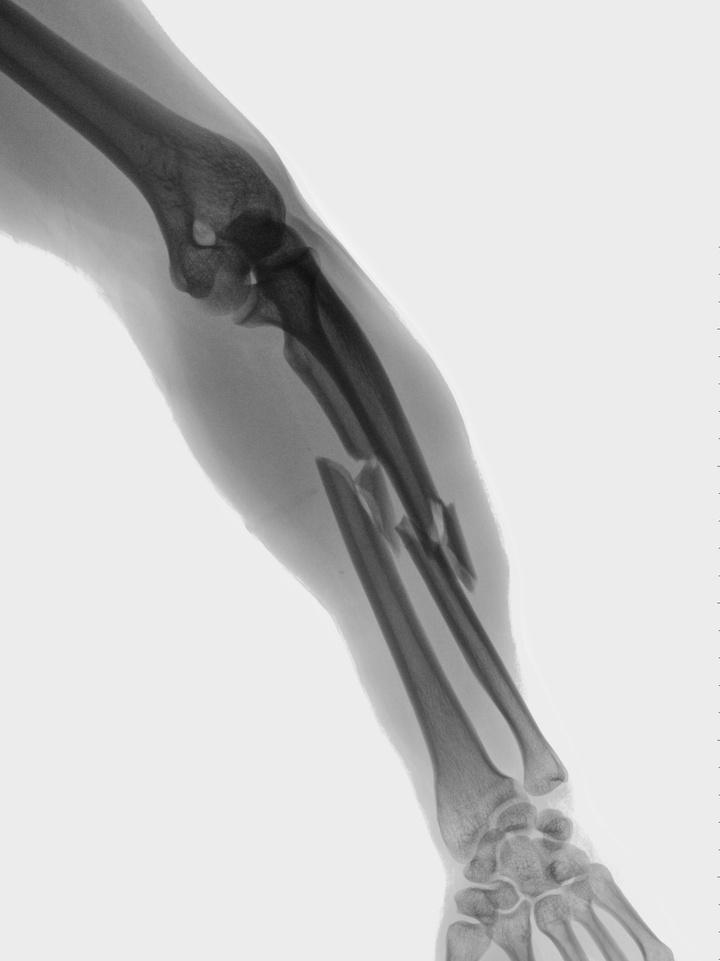

Osteoporosis means "porous" bone and is characterized by either not enough bone formation, excessive bone loss, or a combination of the two.

In osteoporosis, both your bone density and bone quality are reduced which will increase your risk of fracture. Why is this important?